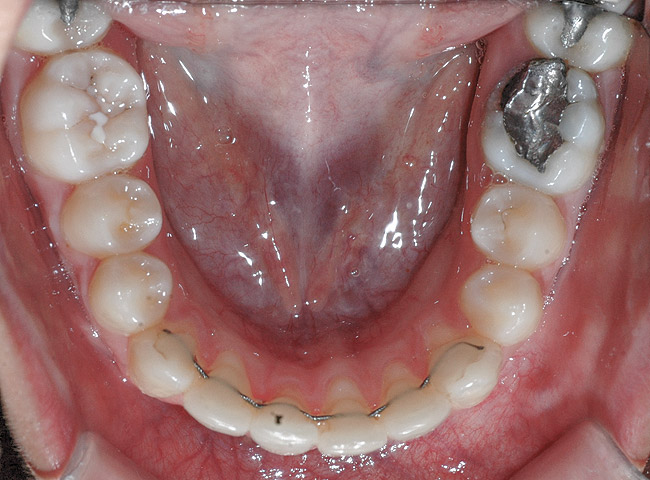

Fig 16. Occlusal view of patient shows the difference in angulation between the affected and the adjacent incisors.

Figure 16

Case Report

A 19-year-old female complaining of gingival recession in the lower right central incisor presented to the authors’ clinic 5 years after completion of orthodontic treatment. The clinical evaluation showed Miller Class II GR accompanied by gingival inflammation (Figure 14). Two years later, despite conservative periodontal treatment, the GR had worsened (Figure 15). The occlusal view shows the presence of a fixed lingual retainer and a significant labial displacement of the root of the affected incisor (Figure 16 and Figure 17). At this stage, orthodontic treatment was considered. The patient was referred for CBCT, which showed no labial bone coverage of the root but 2.5 mm lingual bone thickness at 8 mm distance from the CEJ (Figure 18). After 6 months of orthodontic treatment with fixed appliances (Figure 19), the B-L inclination of the affected tooth was corrected (Figure 20). The frontal clinical view shows narrowing of the GR (Figure 21). Surgical coverage of the exposed root was subsequently performed by connective tissue graft (Figure 22). A long-term stable and esthetic result was achieved (Figure 23).